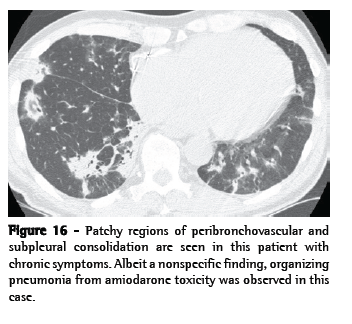

Pattern 3. Increased lung opacity

Increased lung opacity can be described as ground-glass opacity or consolidation. Ground-glass opacity (Figure 15) is increased lung opacity that does not obscure the associated vessels and represents abnormalities below the resolution of HRCT. Consolidation (Figure 16) is increased lung opacity in which the vessels are obscured and represents confluent disease. These findings are quite nonspecific and can reflect diseases that are primarily alveolar, interstitial, or mixed. The differential diagnosis of ground-glass opacity and consolidation overlaps greatly and is predominantly based upon symptom duration: acute or chronic (Chart 8). The distribution of findings (focal, patchy, or diffuse/symmetric) can be helpful in further narrowing the differential diagnosis (Chart 9).